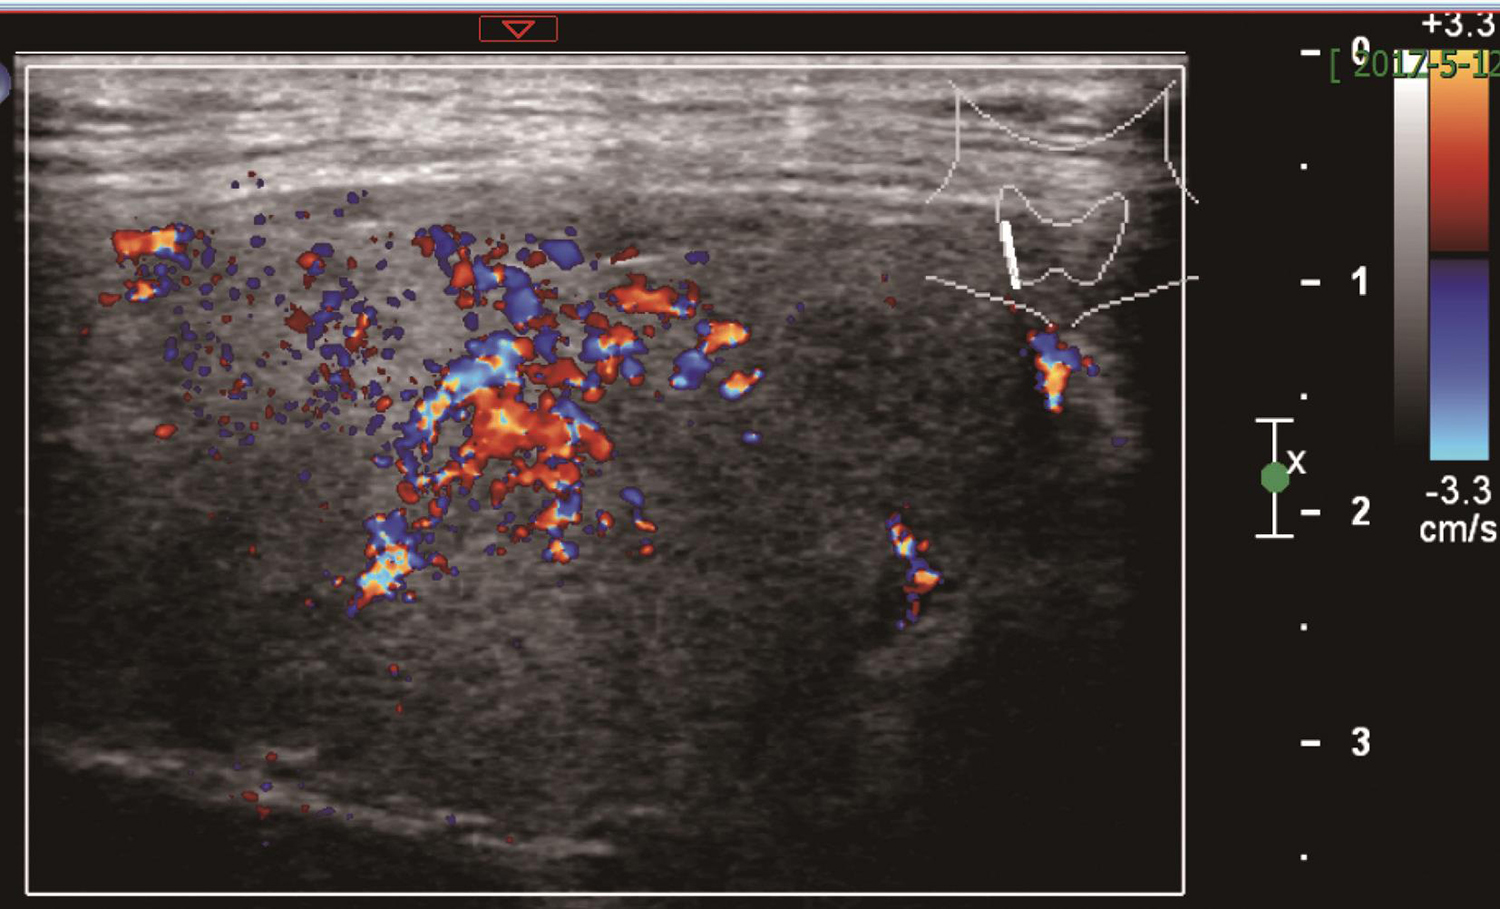

1.2017年5月12日颈部超声

甲状腺右叶肿物,大小约4.2cm×2.0cm,边界欠清楚,形态不规则,CDFI可见血流信号(图1、图2)。左叶低回声结节,大小约0.3cm。右侧气管旁,中下颈及锁骨上多个低回声结节,较大者约1.1cm×0.6cm。余双颈未见肿大淋巴结。

图2 颈部超声示甲状腺右叶肿物CDFI可见血流信号

甲状腺右叶肿物,考虑恶性;甲状腺左叶结节,考虑良性;右颈淋巴结探及。